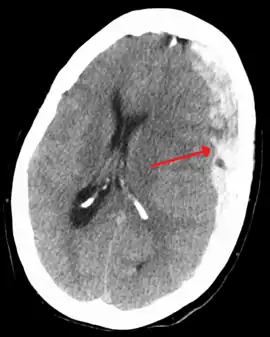

Subdural hematomas occur most often around the tops and sides of the frontal and parietal lobes.[3][2] They also occur in the posterior cranial fossa, and near the falx cerebri and tentorium cerebelli.[3] Unlike epidural hematomas, which cannot expand past the sutures of the skull, subdural hematomas can expand along the inside of the skull, creating a concave shape that follows the curve of the brain, stopping only at dural reflections like the tentorium cerebelli and falx cerebri.

On a CT scan, subdural hematomas are classically crescent-shaped, with a concave surface away from the skull. However, they can have a convex appearance, especially in the early stages of bleeding. This may cause difficulty in distinguishing between subdural and epidural hemorrhages. A more reliable indicator of subdural hemorrhage is its involvement of a larger portion of the cerebral hemisphere. Subdural blood can also be seen as a layering density along the tentorium cerebelli. This can be a chronic, stable process, since the feeding system is low-pressure. In such cases, subtle signs of bleeding—such as effacement of sulci or medial displacement of the junction between gray matter and white matter—may be apparent.

Fresh subdural bleeding is hyperdense, but becomes more hypodense over time due to dissolution of cellular elements. After 3–14 days, the bleeding becomes isodense with brain tissue and may therefore be missed.[20] Subsequently, it will become more hypodense than brain tissue.